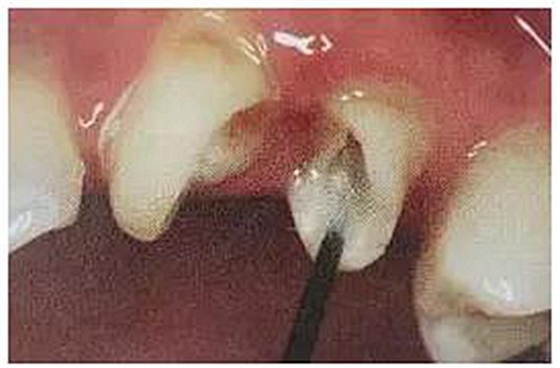

第一步,去除27的銀汞充填材料,發(fā)現(xiàn)髓腔破壞大,繼發(fā)齲明顯,牙體變色。

絢彩AT無飾瓷全形態(tài)氧化鋯產(chǎn)品體驗(yàn)+全冠和嵌體微創(chuàng)修復(fù)后牙

第二步,拆除26舊修復(fù)體,因?yàn)槊芎隙雀?,拆冠費(fèi)了不少時(shí)間。

拆冠對26的頰舌側(cè)肩臺有所破壞,牙齦少許損傷。暫時(shí)臨時(shí)牙修復(fù)保護(hù)基牙。